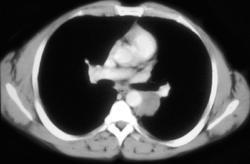

Rhinoscleroma